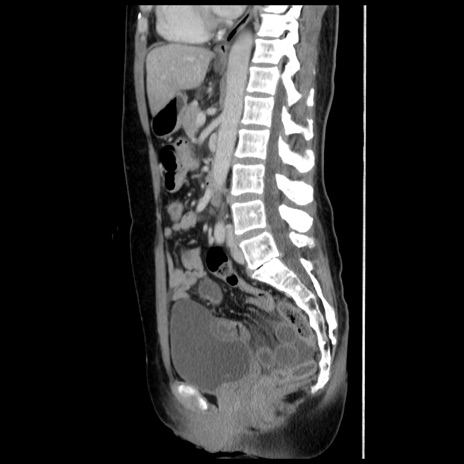

症例10(矢状断像)

【症例】 50歳代女性

【主訴】 腹痛

【現病歴】前日生レバーを食べた。今朝に排便あり。 昼前に突然発症の腹痛を生じ、当院救急外来を受診した。

【既往歴】 子宮筋腫にてで子宮全摘後

【身体所見】 意識清明、腹部:平坦、軟、下腹部やや左を中心に圧痛・反跳痛あり、筋性防御あり

【データ】WBC 7800、CRP 0.07